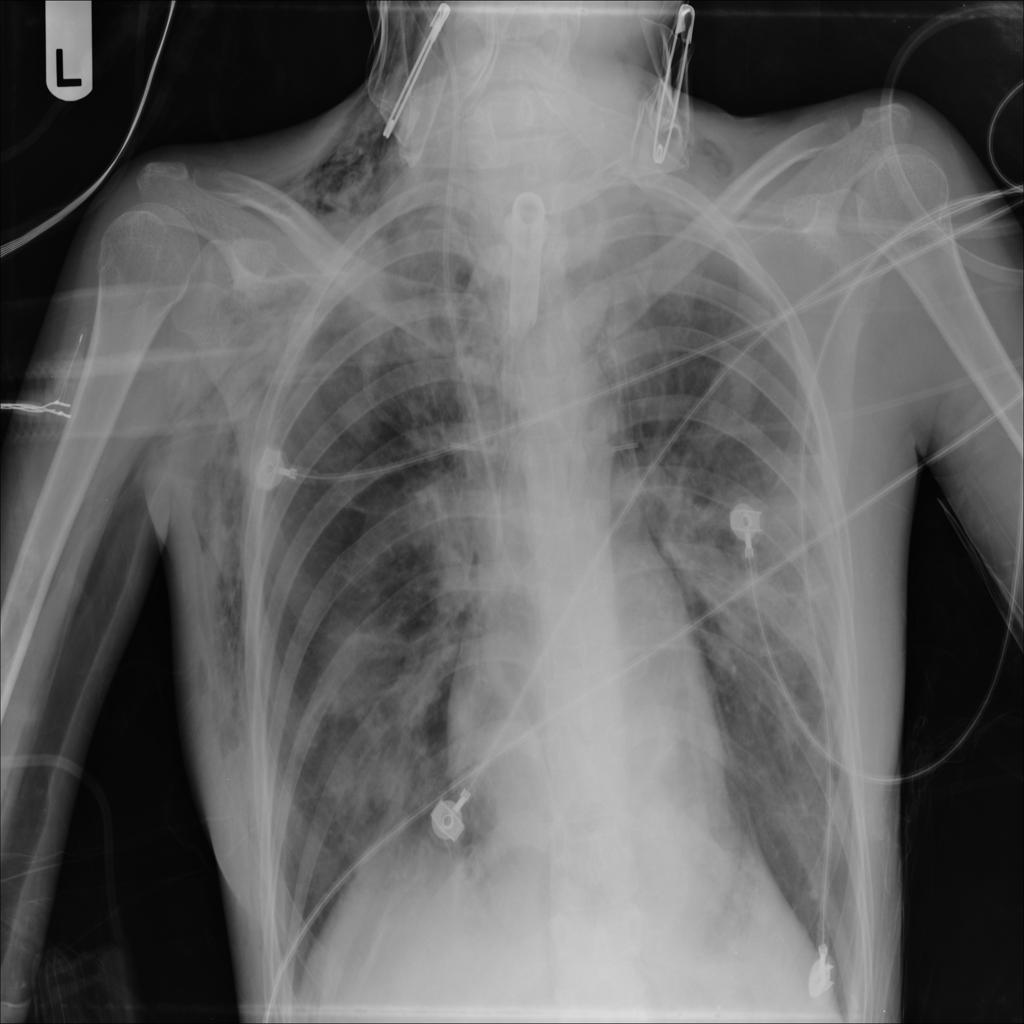

Showing up to 90 reference images for Emphysema.

PAT-0E82 · IMG-000Emphysema

PAT-0E82 · IMG-000

AP